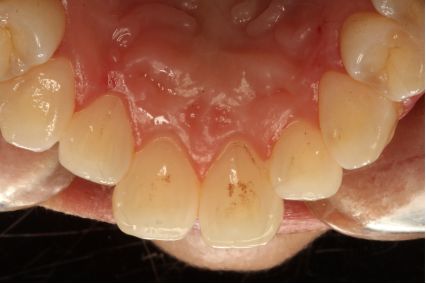

超声洁刮治术后5周

采用PT5牙周治疗仪进行全口超声龈上洁治术、超声龈下刮治术。术后5周复查可见牙龈炎症明显减轻,仍有轻度炎症,复查发现患者口腔卫生维护欠佳,再次进行口腔卫生宣教。